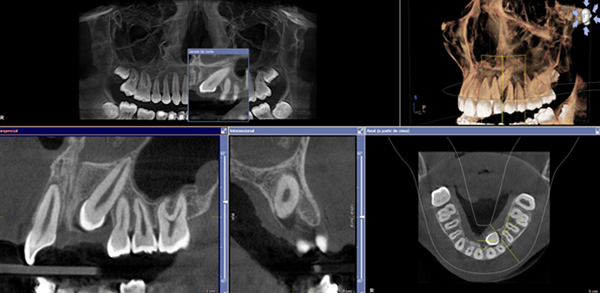

A TCCB representa um grande avanço na área de imaginologia e difere da radiografia convencional, pois permite a visualização tridimensional das estruturas ampliando as possibilidades de diagnóstico. É indicada para todas as áreas da odontologia, como para planejamento de implantes, localização de dentes inclusos, analise de canais radiculares entre muitas outras. A dose de radiação é muito reduzida, dado que trabalha com miliamperagens baixas, principalmente quando comparada com a tomografia computadorizada medica. Na Doc Ideal trabalhamos com tomógrafos de FOV 8x8 cm que adquirem toda a arcada dentaria e voxel de 0,1 mm que permitem uma qualidade de imagem muito superior.